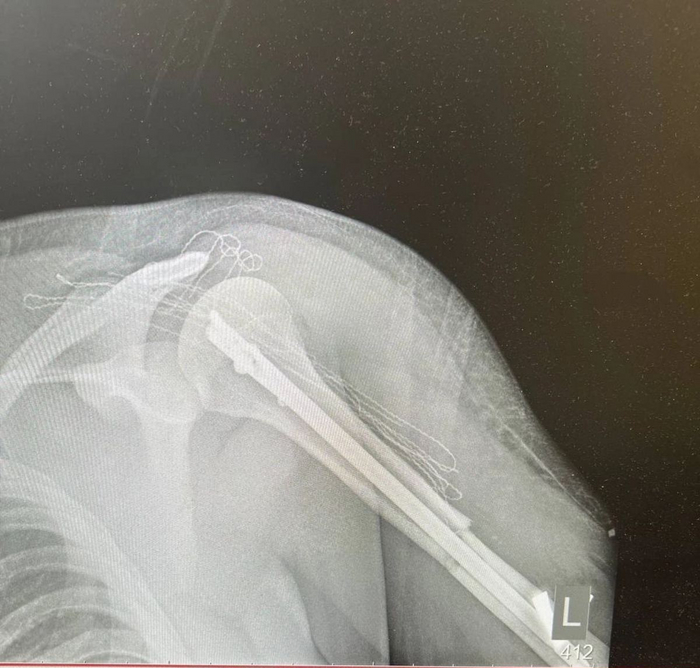

Ну и я - перелом плечевой кости левой руки и ЧМТ...

Последнее, что помню - это касание автомобилей, сам момент, дальше все отрывками, так как большую часть времени был без сознания. Помню как МЧС будят, сообщают, что доставать будут, помню как в скорой что-то ставят, помню, что в трубочку дышать заставляют для проверки на алкоголь, но не помню в машине или уже в скорой, и помню уже больницу, как гипс накладывают, тот что на фото выше.

кусок металла в моей руке